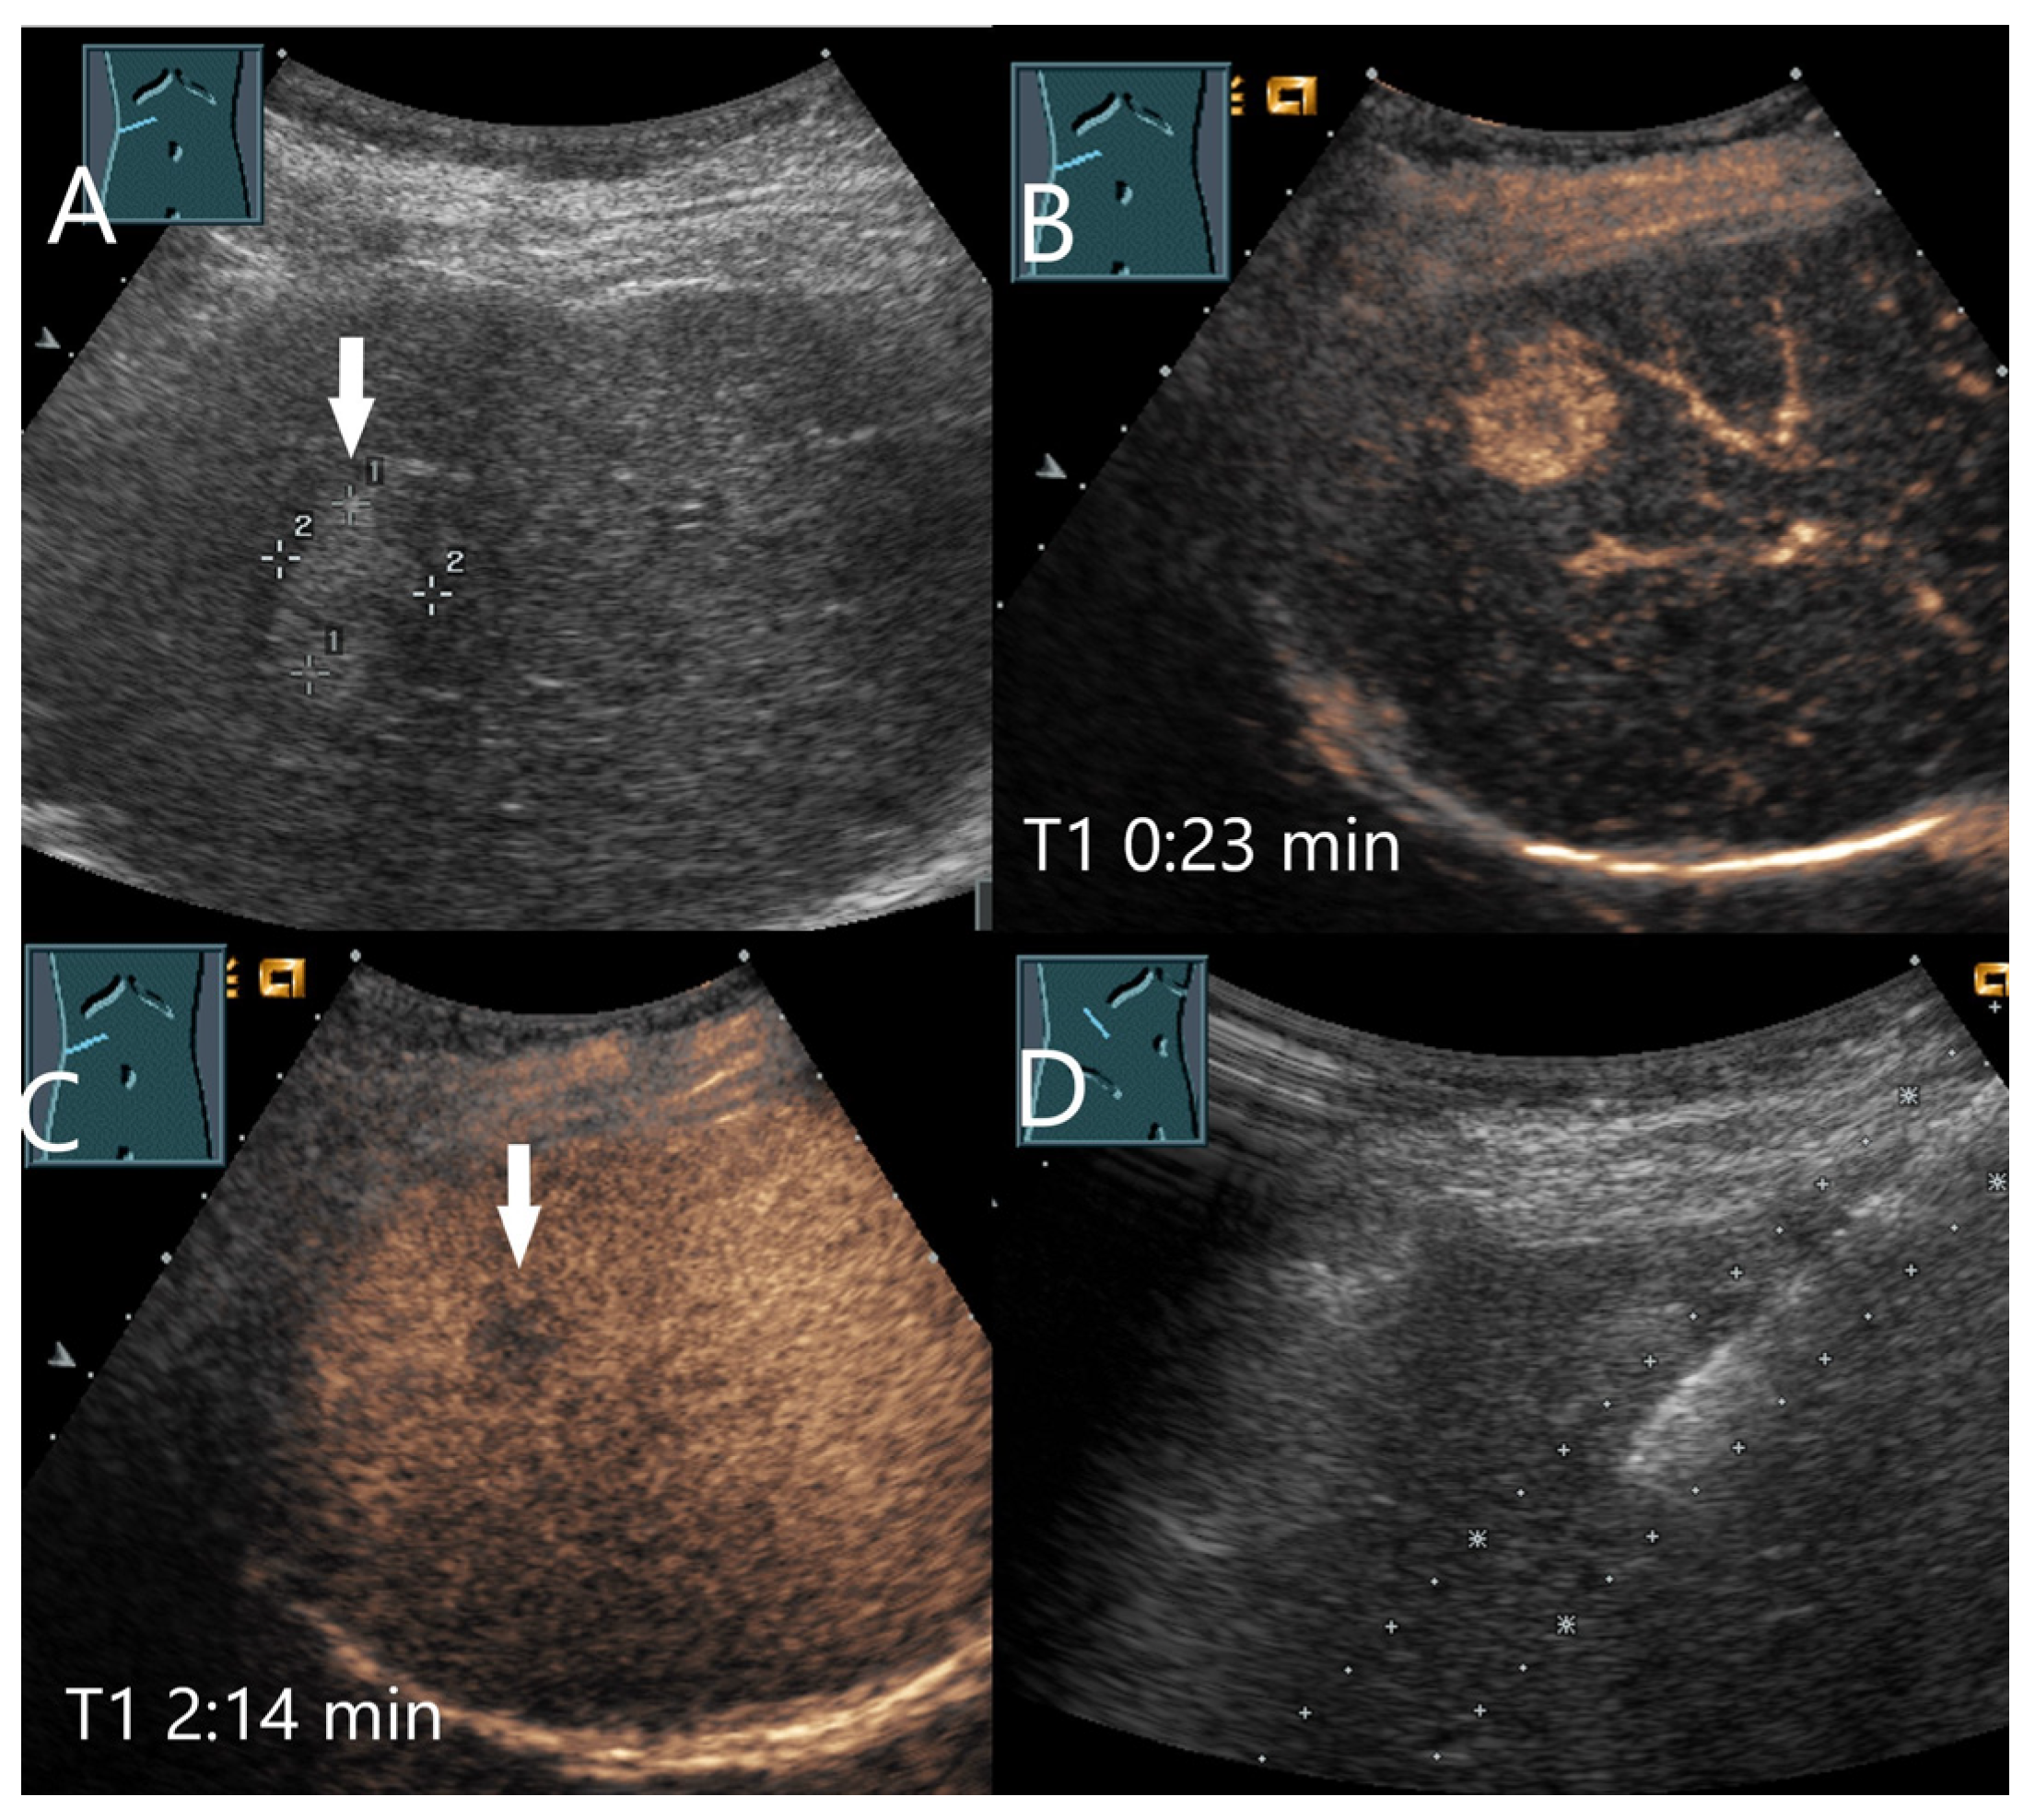

| Hemangioma | Hyperechoic, beyond liver veins, hypoechoic in steatosis and with shunts. | Peripheral globular enhancement, centripetal filling. Rapid homogeneous filling in shunt hemangiomas. | Hyperenhancement and isoenhancement. | Permanent video loops with destruction of the UCA bubbles and slow refill. Fibrosis. |